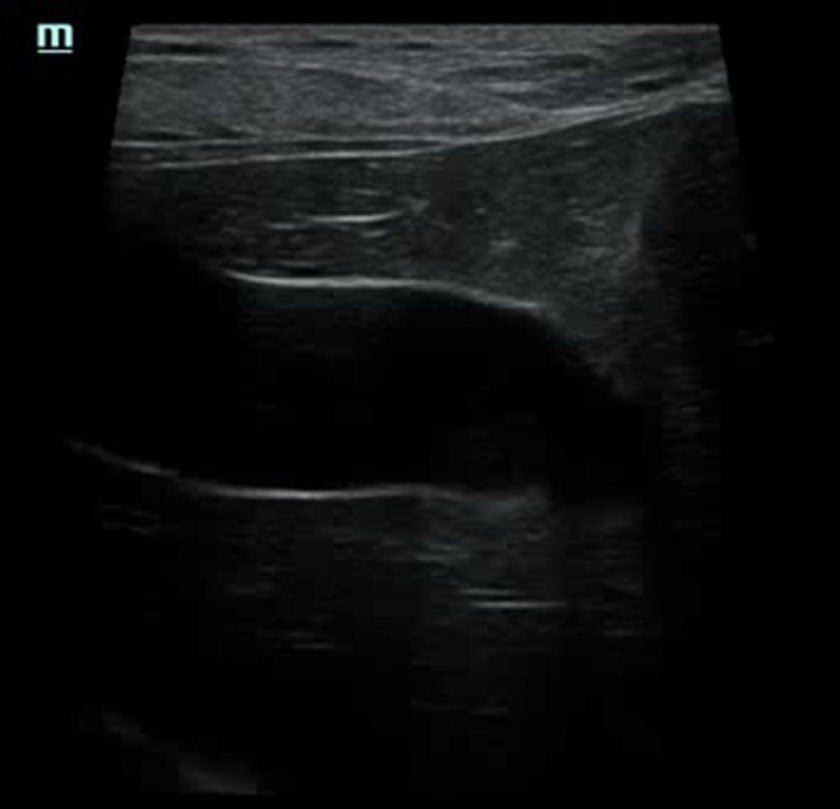

Собака Булка поступила на прием терапевта с жалобами на дрожь и болевой синдром, а также рвоту, диарею и одышку. При сборе анамнеза выяснилось, что вчера помимо обычной порции корма Булка получила пельмень со сметаной. Врач отправил собаку на УЗИ, где были обнаружены признаки острого холецистита - выраженное утолщение стенки желчного пузыря и следы свободной жидкости в брюшной полости.

По анализам крови также отмечались выраженная билирубинемия, повышение трансаминаз и умеренный лейкоцитоз. После курса терапии Булка чувствовала себя отлично, а на контрольном УЗИ стенка желчного пузыря выглядела абсолютно нормальной.